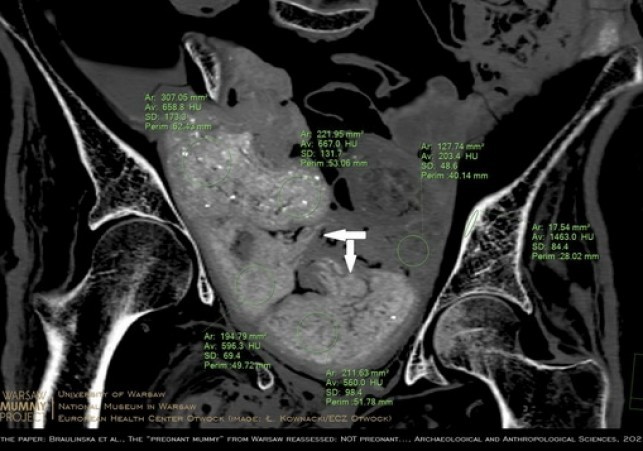

warszawska mumia

Mumia egipska z Warszawy nie była w ciąży - w jej miednicy znajdują się... pakunki

Nie płód, ale kilka zawiniątek znajduje się w miednicy mumii kobiety prezentowanej w Muzeum Narodowym w Warszawie - dowodzi zespół naukowców. W jednym… Czytaj więcej